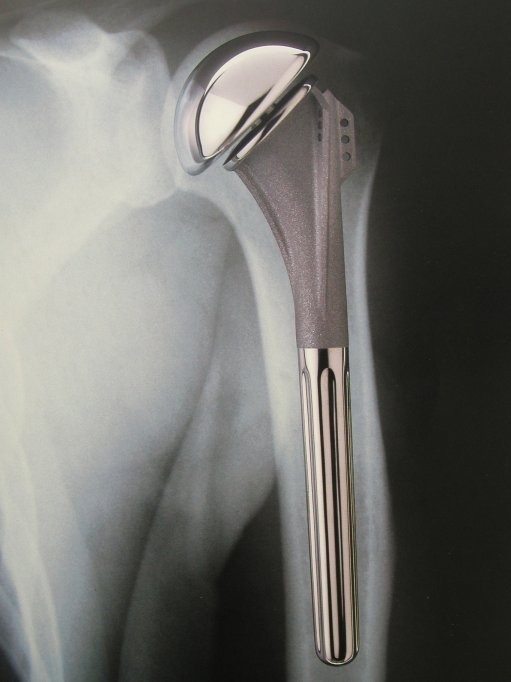

Artificial shoulder joint

X-ray of the special prosthesis